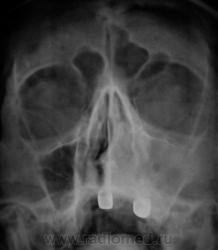

Линейка. Первый срез.

Второй срез.

Третий срез.

Вроде бы и ДА, а вроде бы и НЕТ...какое то двойственное впечатление: есть нечеткость наружной стенки на первом среже, есть связь с носовым ходом на всех трех, есть небольшое увеличение пазухи на третьем....а в целом....все таки больше ЗА, чем против...

Четвертый срез.

Последний срез.

Увеличение обьема - однозначно....

На мой взгляд, информативные срезы 4 и 5, ну, конечно, обработанный 3!